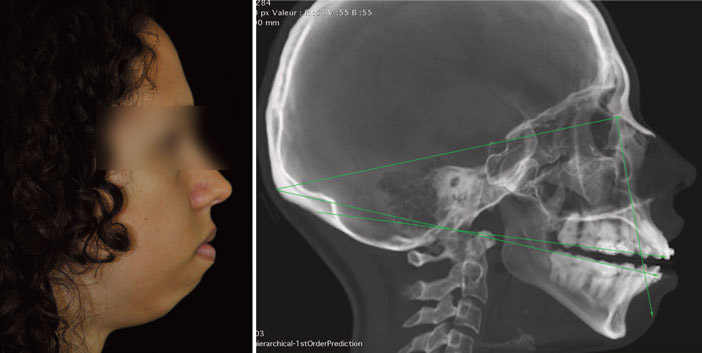

sourire gingival

• La chirurgie orthognatique

Comment harmoniser le sourire et le visage ?